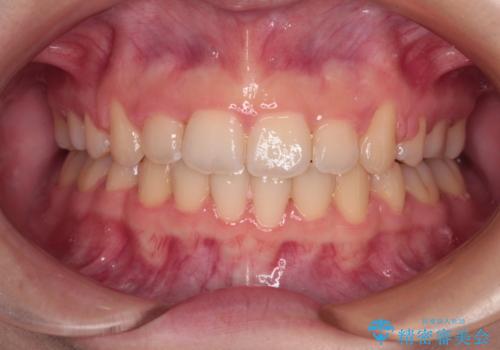

- 上下の前歯が突出しており、口が閉じにくいとのことで来院された患者様です。

上下前歯が著しく前突している状態であったので、上下左右の第1小臼歯4本を抜歯し、ワイヤー装置にて矯正治療を行うこととしました。

舌の突出癖により、前突になったと考えられたため、舌のトレーニングをしっかりと行うよう指導しました。